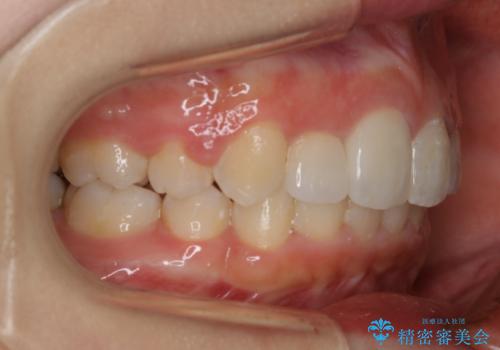

矯正治療でご自身の歯を移動して閉じることにしました。

また、咬んだときに下の前歯が隠れる過蓋咬合でしたが、矯正治療で改善しました。

矯正治療で根の向きも修正したため、左右対称に審美的なセラミックを入れることができました。